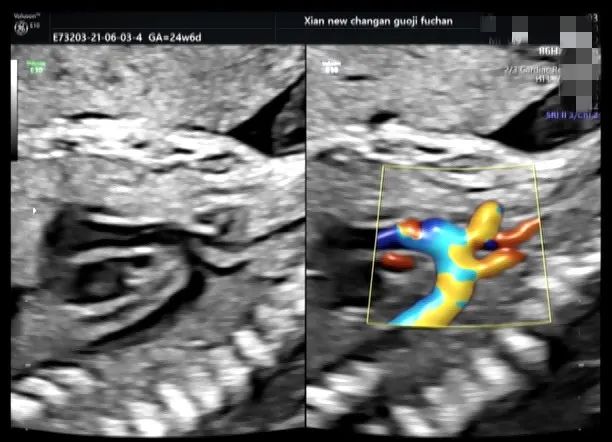

病例五

完全性大动脉转位

孕妇 XXX 女 28 岁 G1PO 孕 18W1D

在本院行常规筛查时发现心脏结构异常,主动脉发自与右心室,肺动脉发自于左心室,室间隔膜周部可见 3 mm 的回声中断,余结构未见异常。

为进一步评估生后手术情况,遂前往西京胎心诊断中心,诊断结论与本院一致。

完全型大动脉转位 ( TGA):即房室连接一致而心室与动脉连接不一致。心房与心室连接正常,右心房通过三尖瓣与右心室连接,左心房通过二尖瓣与左心室连接,但是大血管的连接调转肺动脉发自左心室,主动脉发自右心室。两条大动脉呈并列走行。D-TGA 可以是孤立存在的,也可伴有其他心脏异常。室间隔缺损和肺动脉狭窄 (左室流出道梗阻) 都是 D-TGA 的常见并发症,可单独存在,也可联合发病。

完全性大动脉转位也属于紫绀型心脏病,临床出现紫绀、呼吸困难能症状,所以出生后不久就需要进行大动脉调转手术。